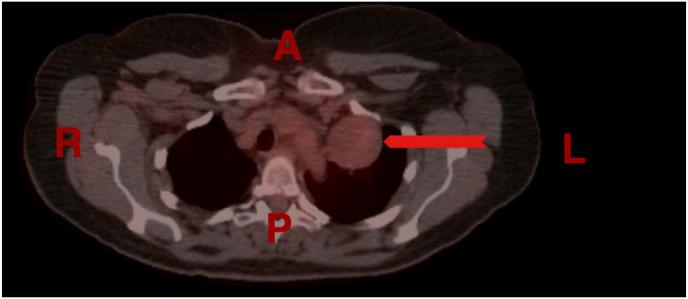

Solitary fibrous tumors of the pleura (SFTPs) are rare neoplasms of mesenchymal origin most commonly arising in the pleura and have a benign biological behavior in the majority of cases. Most patients with SFTPs are asymptomatic; however, symptoms are mostly related to the mass effect within the thoracic cavity. Chest computed tomography (CT) scanning is the radiographic test of choice, but findings lack specificity. Surgical resection is the treatment of choice for most patients. Long-term survival after resection of benign SFTPs is excellent. In this case series, we present two females, one presented with shortness of breath (SOB) and nonproductive cough and the other one was referred because of abnormal x-ray findings. The histological as well as the immunohistochemical examination revealed the mass to be a solitary fibrous tumor of the pleura.

胸膜孤立性纤维瘤(SFTPs)是一种罕见的间叶源性肿瘤,最常起源于胸膜,大多数病例具有良性生物学行为。大多数SFTPs患者无症状;然而,症状大多与胸腔内的肿块效应有关。胸部计算机断层扫描(CT)是首选的影像学检查,但检查结果缺乏特异性。手术切除是大多数患者的首选治疗方法。良性SFTPs切除后的长期生存率很高。在本病例系列中,我们报告了两名女性,一名表现为呼吸急促(SOB)和干咳,另一名因X线检查结果异常而转诊。组织学及免疫组化检查显示该肿块为胸膜孤立性纤维瘤。